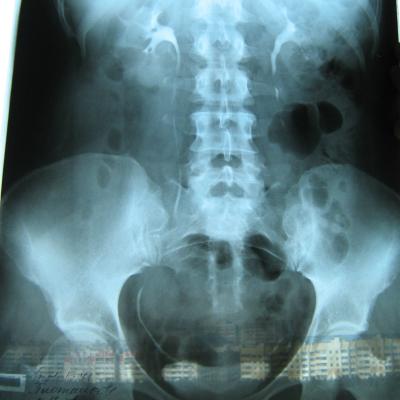

Была сделана операция 04.07.2012г по поводу нефропексии правой почки поясничной мышцей с помощью разреза. После операции болит правая сторона живота и в спине и в пояснице был затронут нерв, и до сих пор правая нога до колен не отходит спереди и сбоку. Через полтора месяца после операции образовался отек, пошло воспаление сзади на спине, потому что был затронут нерв. Сделала урографию через 4 месяца после операции. Если вас не затруднит, посмотрите пожалуйста снимки, правильно ли располагается мочеточник правый после операции. Скажите пожалуйста, посмотрев мои снимки, правильное ли расположение мочеточника и почему болит правая сторона живота все это время, и каким исследованием теперь после операции проверить что там творится в животе, что там затронуто? Все указывает на то что был затронут нерв, оперирующий врач говорит что не может быть такого, а я уже почти всю ногу правую не чувствую

Снимки прикрепляю

Абсолютно нормальное расположение почки и мочеточника . Но ведь и онемение нижней конечности с положением почки не связано. Есть такое понятие "футлярный синдром"- после вынужденного положения конечности. Проконсультируйтесь с неврологом.